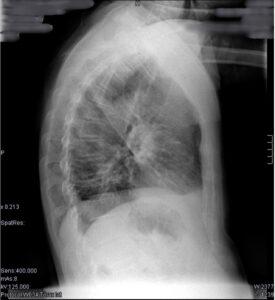

Rx L de tórax